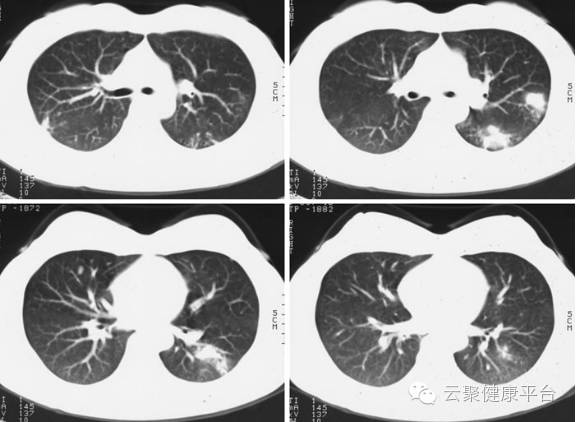

CT像把土豆切片看,检查原理是X光会分层穿过人体,之后通过电脑计算后二次成像,就像把土豆切成片来看。优点是可以分层看,可以显示出更多的组织信息。

CT看肺部:胸部断层像切面包片观看内部结构

3、胸部——粗看X光片,细看CT

X光胸片可粗略检查心脏、主动脉、肺、胸膜、肋骨等,可以检查有无肺纹理增多、肺部钙化点、主动脉结钙化等。胸部CT检查显示出的结构更清晰,对胸部病变检出敏感性和显示病变的准确性均优于常规X光胸片,特别是对于早期肺癌确诊有决定性意义。但是常规CT检查的辐射剂量高于X光(开源超炫速CT除外)。核磁对于肺部疾病的诊断,应用非常有限。